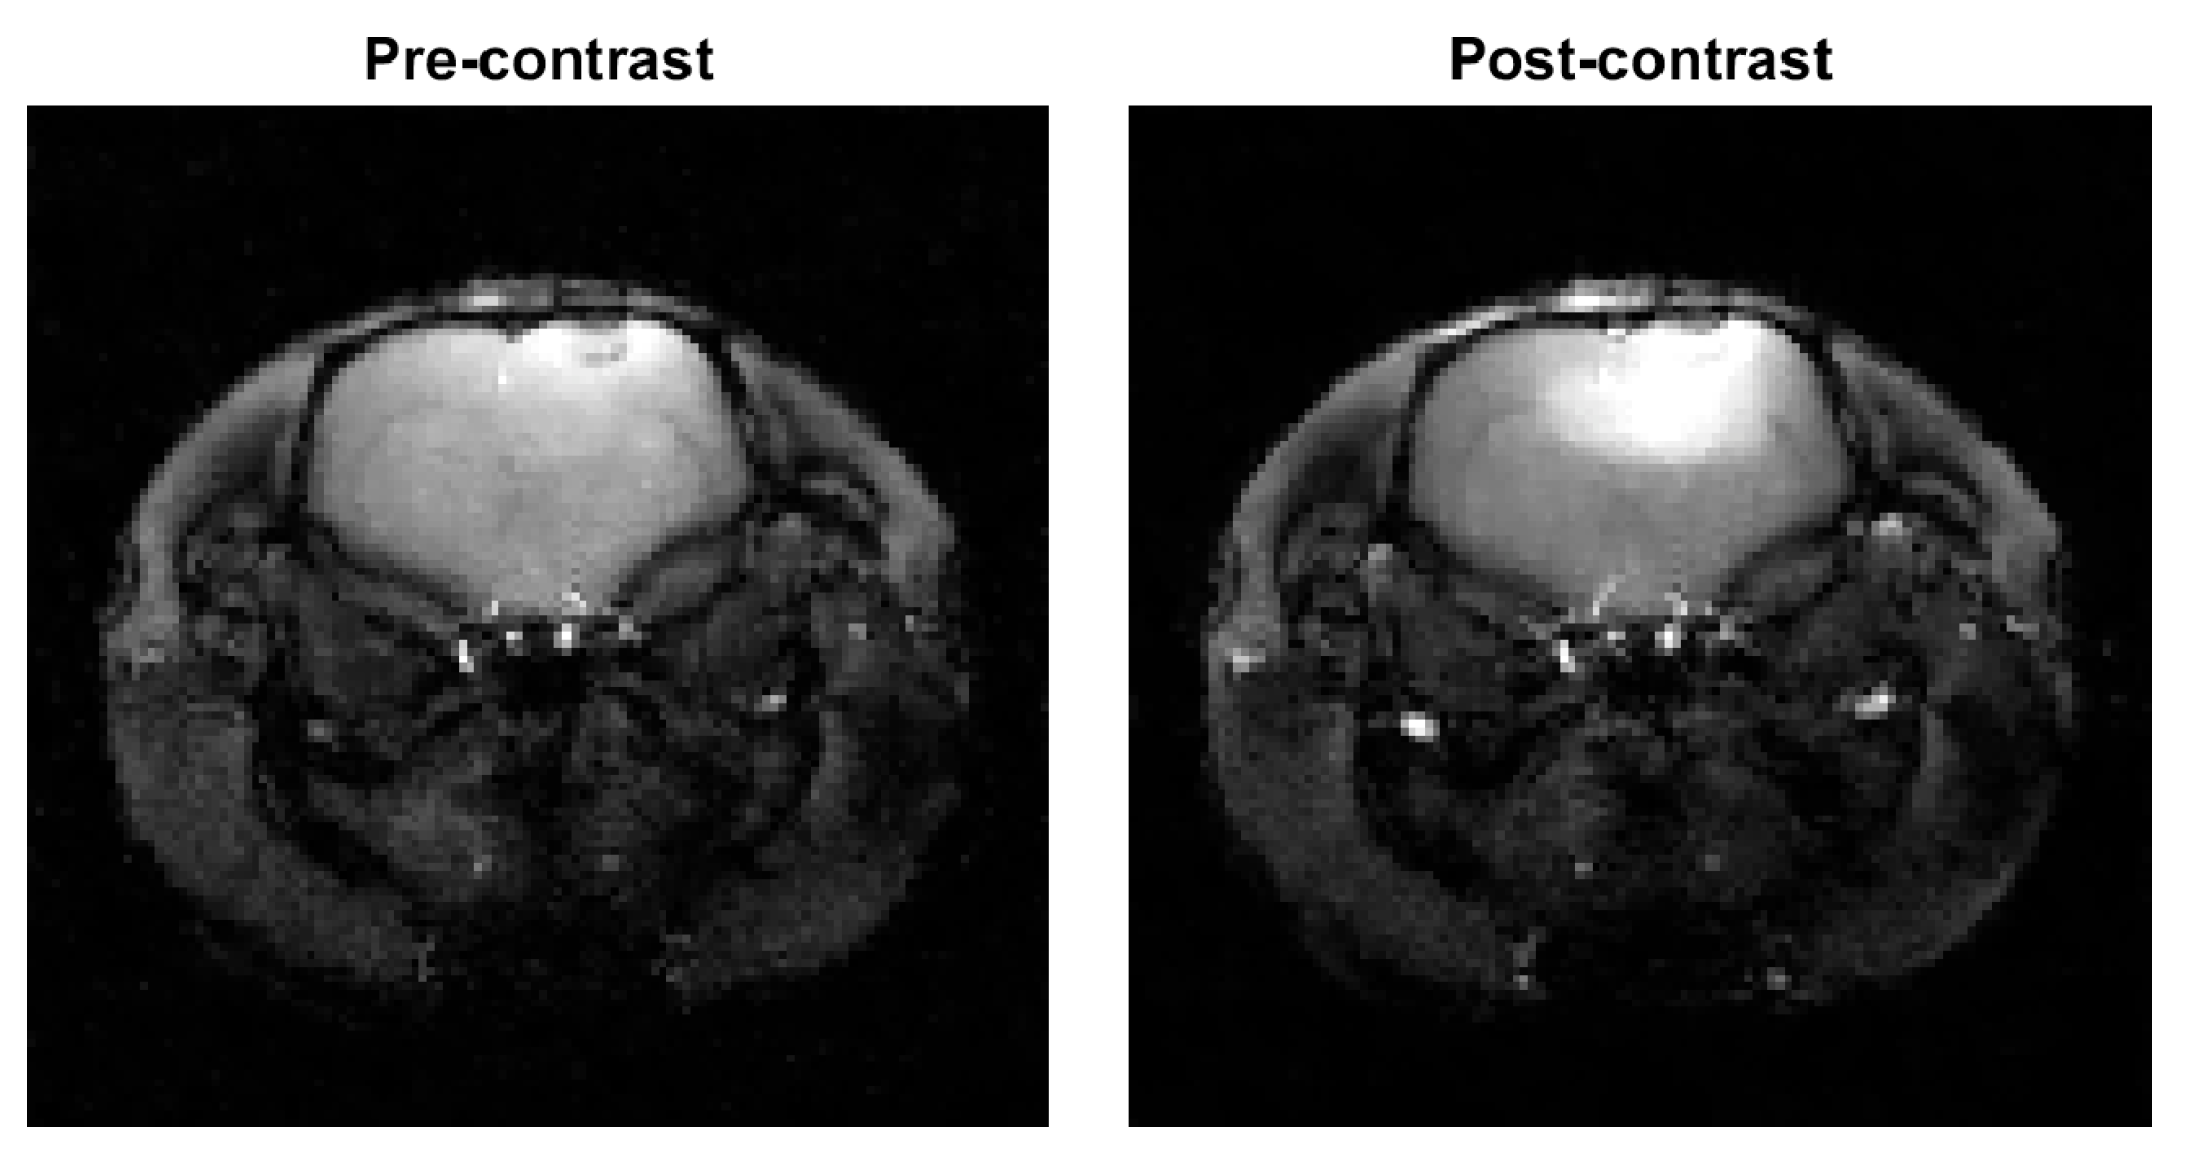

3.2. In Vivo Measurements from a Rat Glioma Model